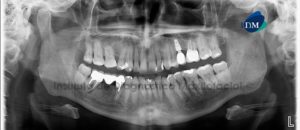

Paciente femenino de 27 años de sexo femenino acude al Instituto de Diagnóstico Maxilofacial para evaluación preoperatoria de cirugía ortognática. A la evaluación de la